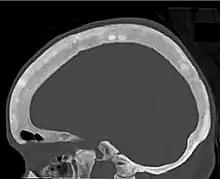

Renal osteodystrophy is usually diagnosed after treatment for end-stage kidney disease begins; however the CKD-MBD starts early in the course of CKD.[1][6] In advanced stages, blood tests will indicate decreased calcium and calcitriol (vitamin D) and increased phosphate, and parathyroid hormone levels. In earlier stages, serum calcium, phosphate levels are normal at the expense of high parathyroid hormone and fibroblast growth factor-23 levels. X-rays will also show bone features of renal osteodystrophy (subperiostic bone resorption, chondrocalcinosis at the knees and pubic symphysis, osteopenia and bone fractures) but may be difficult to differentiate from other conditions. Since the diagnosis of these bone abnormalities cannot be obtained correctly by current clinical, biochemical, and imaging methods (including measurement of bone-mineral density), bone biopsy has been, and still remains, the gold standard analysis for assessing the exact type of renal osteodystrophy.[6][16]

18. 1 2 3 4 5 6 7 Patel, Anish A.; Ramanathan, Rohit; Kuban, Joshua; Willis, Marc H. (2015). "Imaging Findings and Evaluation of Metabolic Bone Disease". Advances in Radiology. 2015: 1–21. doi:10.1155/2015/812794. ISSN 2356-6876.